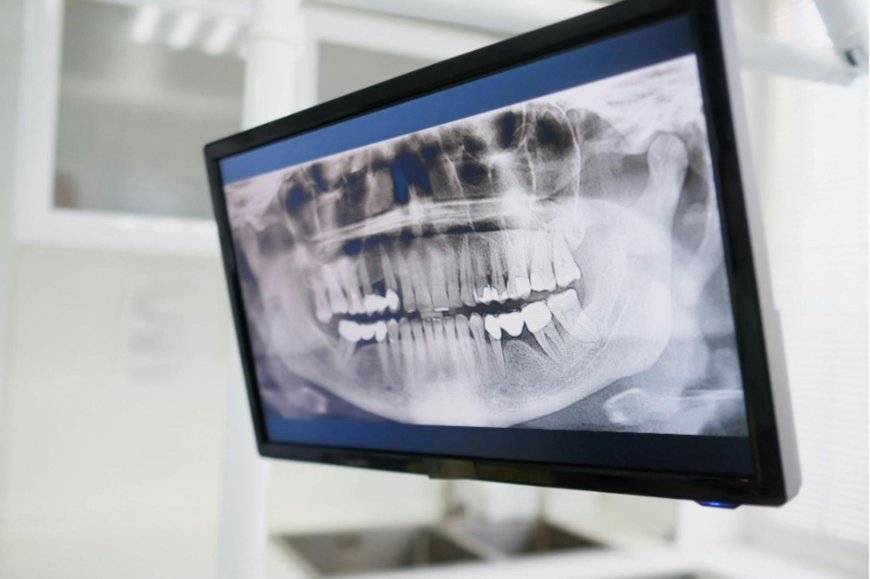

全口掃描 X 光攝影(panoramic x-ray)。(圖片來源/pexels;授權轉載自科技大觀園,下同)